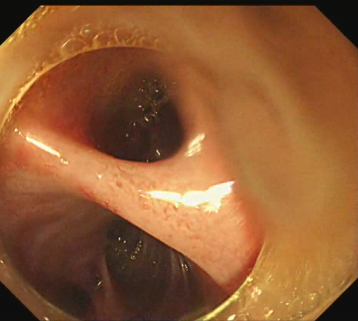

内镜下胆肠吻合口通畅,小肠镜可直接到达肝内胆管,胆管内可见含絮状物胆汁

当时考虑可能由于胆肠吻合口过于通畅,肠液反流才导致胆管炎反复发作,但还是决定用球囊堵塞造影。

造影见肝右叶胆管显影,虽然肝左叶胆管内空气显影,但是始终不见造影剂进入。反复寻找,终于找到下图中一个潜在的小孔